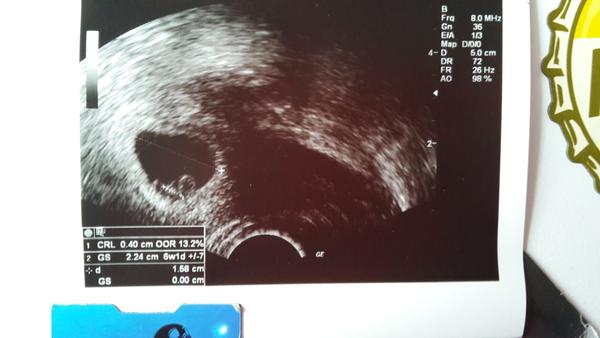

Ahoj Holky mozte mi povedat ci je normalny takyto UZ v 6tt? Ultrazvuk na foto mam z minuleho tyzdna, doktor jedine co povedal ze tam este nic nevidi ale inak sa nevyjadril :( dnes som bola zas na kontrole a vyjadrenie bolo, ze vidi len flíček ale bez plodu :( zacinam mat divny pocit, skoncili mi tehot. priznaky a vobec sa necitim ako tehotna. dalsiu kontrolu mam o 14 dni. Pokial mate s takymto UZ skusenosti moc dakujem za radu

ahojky tak dneska kontrola dopadla na 1, miminko ma 3cm a srdicko bilo ako o zavod 🙂